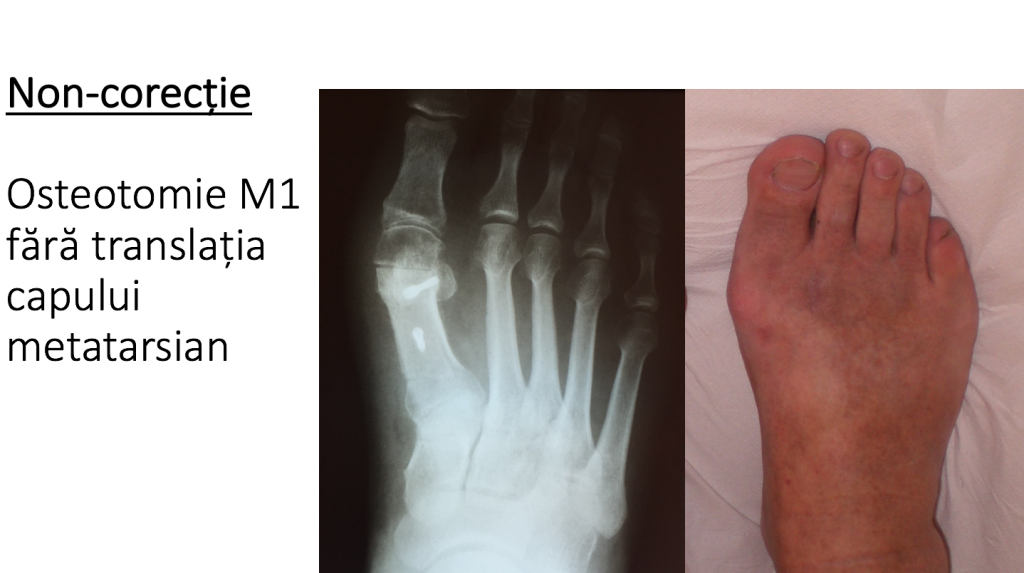

1. NON-CORECTIA

- persistenta proeminentei ("montului") se observa imediat post-operator;

- non-corectia poate fi urmarea aplicarii incorecte a tehnicilor moderne (scarf, chevron etc);

- non-corectie: primul metatarsian ramane proeminent;

- deformatia ramane aceeasi sau chiar se agraveaza, datorita procedurilor de tip mutilant articular;

- translatia insuficienta a metatarsianului 1 (dupa osteotomie) este cauza cea mai frecventa a hipo-corectiei;

- osteotomia metatarsianului 1 (scarf, chevron etc) produce hipo-corectie in cazul translatiei insuficiente a fragmentelor;